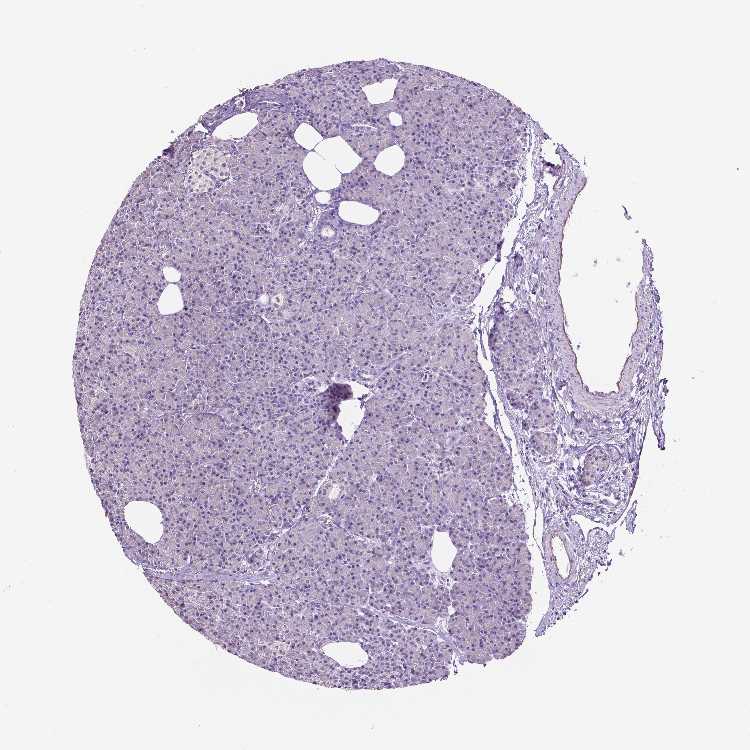

PANCREAS - Antibody stainingi

Antibody staining in the annotated cell types in the current human tissue is reported as not detected, low, medium, or high, based on conventional immunohistochemistry profiling in selected tissues. This score is based on the combination of the staining intensity and fraction of stained cells.

Each image is clickable and will lead to virtual microscopy that enables deeper exploration of all samples and also displays staining intensity scores, fraction scores and subcellular localization as well as patient and tissue information for each sample.

Antibody HPA069097

Exocrine glandular cells Not detected

Pancreatic endocrine cells Not detected